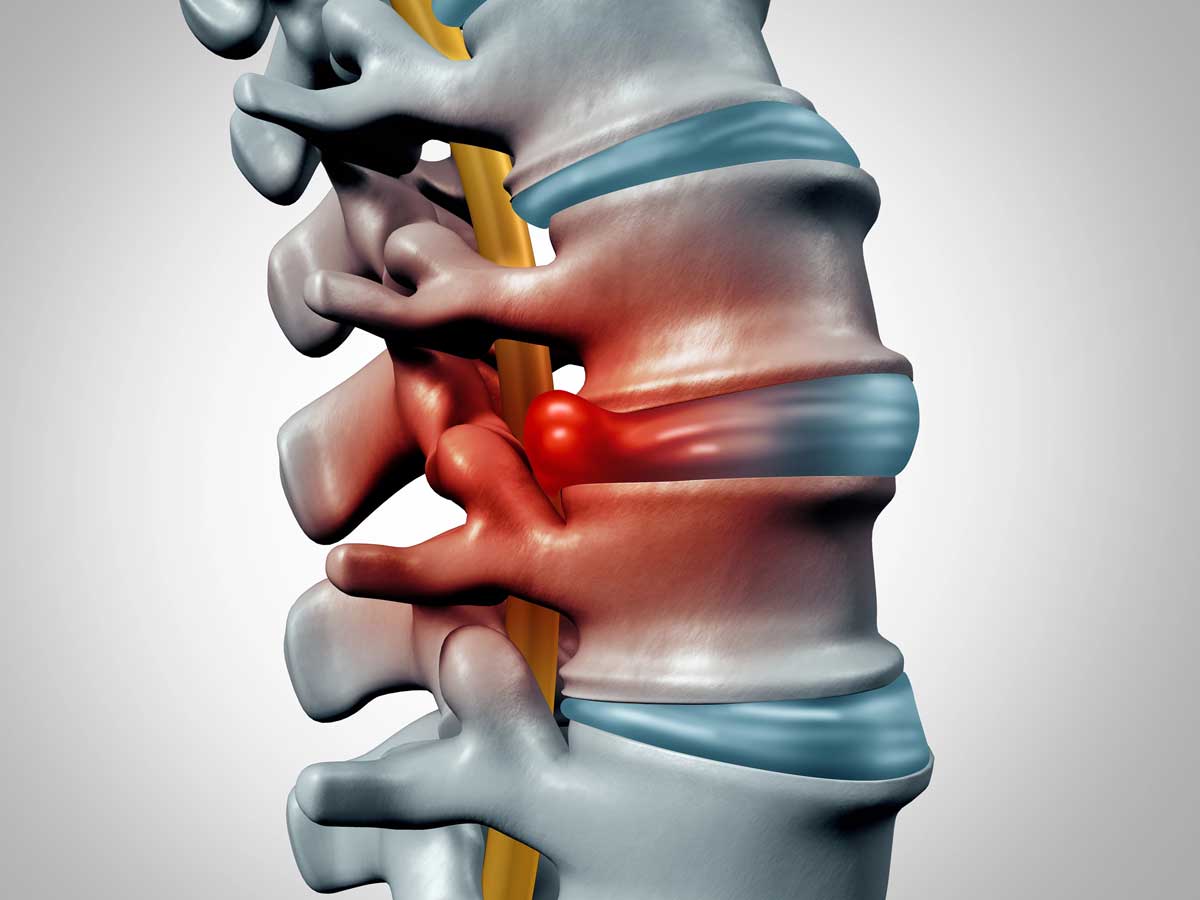

Spinal discs act as cushions between the vertebrae. Each disc contains a soft, gel-like center surrounded by strong outer fibers. When discs are healthy, they support smooth movement and allow the spine to bend, twist, and absorb shock.

Trauma or stress, such as improper lifting, slips and falls, or motor vehicle accidents—can disrupt the disc’s structure. When this happens, different types of disc problems may develop:

- Herniated disc, Occurs when the inner core breaks through the outer layer

- Disc protrusion, The disc bulges outward, often irritating or pressing on nearby nerves

- Disc prolapse, A more advanced condition where disc material shifts out of its normal position between the vertebrae